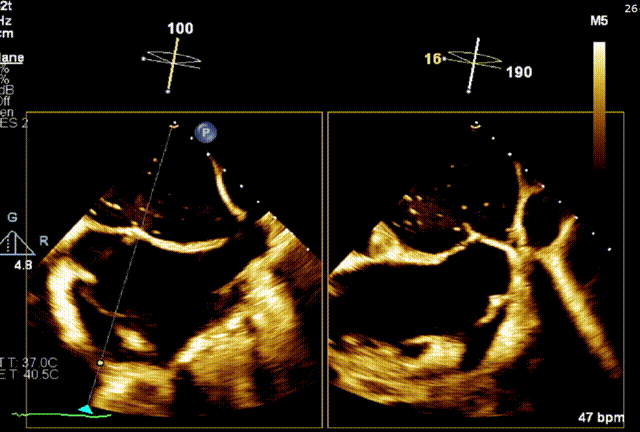

手术结果

患者因严重脊柱侧弯无法平躺,只能处于半靠卧状态,这给麻醉工作带来极大阻碍。更具挑战的是,脊柱侧弯导致患者心脏解剖结构发生极大改变,房间隔穿刺路径极度迂曲,大大增加了手术操作难度。手术团队借助CT三维解剖重建,精准明确畸形结构,使用MitraClip™G4完成瓣膜精准修复,克服重重困难在半靠位完成手术。术后经食道超声评估,患者二尖瓣返流量<1+,压差1.5mmHg,手术获圆满成功。该病例的突破,彰显了团队在复杂心脏介入领域的技术实力,为同类高难度患者的治疗提供了重要参考。